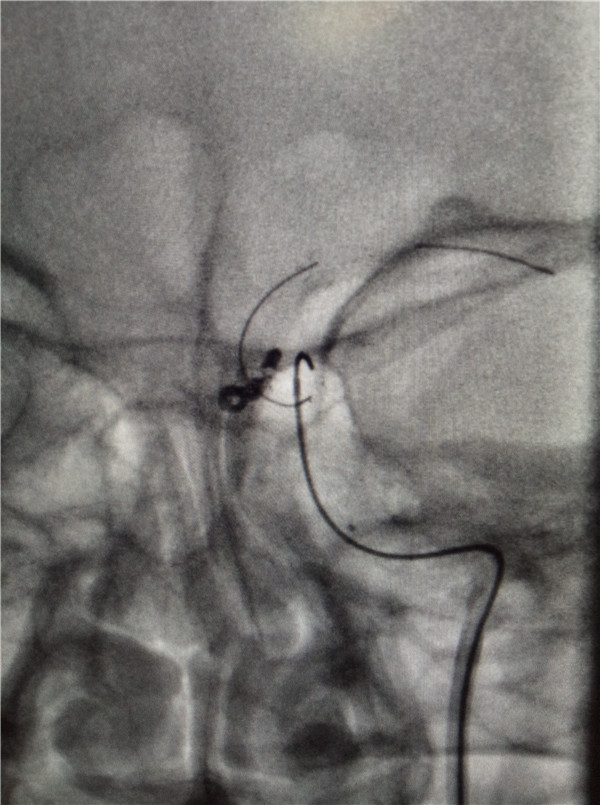

9月5日下午,我院神經(jīng)外科在安醫(yī)附院王曉健主任的幫助下,開展了我院首例顱內(nèi)動脈瘤介入栓塞術(shù),手術(shù)完成順利,術(shù)后造影載瘤動脈通暢,瘤體不顯影。

此次介入手術(shù)在麻醉科及導管室的大力支持下完成,為手術(shù)的順利完成提供了充分的保障,也充分體現(xiàn)了一個綜合性醫(yī)院各個科室之間協(xié)作的重要性。